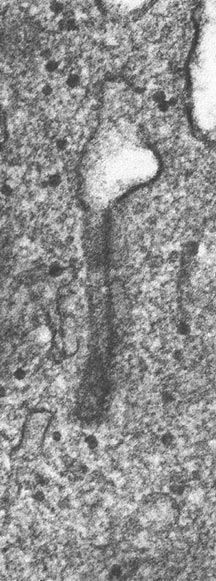

- Birbeck Granules: Electron Microscopy demonstrates granules that often take the form of a tennis raquet and form from complex invaginations of the cell membrane

- Vimentin, CD1 and S-100 positivity